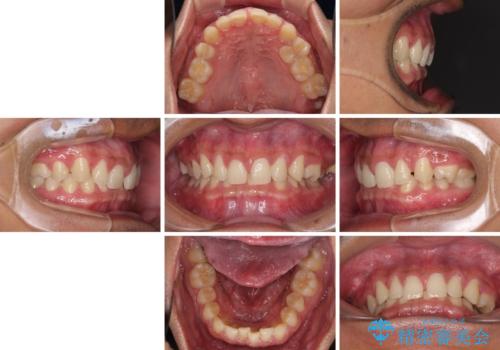

著しいディープバイトと隙間だらけの歯列

- 歯のデコボコと歯の隙間を気にして来院された患者様です。

隙間の原因は、埋伏や前後に重なってしまっている上顎小臼歯と、下の前歯が見えなくなるくらいのディープバイトで、それらを改善する必要がありました。

アンカースクリューを用いて下に位置している上顎前歯を持ち上げるとともに、ワイヤー装置によりディープバイトの原因である奥歯の傾斜を改善することで、矯正治療を行っていくこととしました。

顕著なディープバイトのため、頻繁に装置が脱離することがあり、治療期間が想定よりも長くかかることがありますが、当初の予定期間で無事に治療を終えることができました。